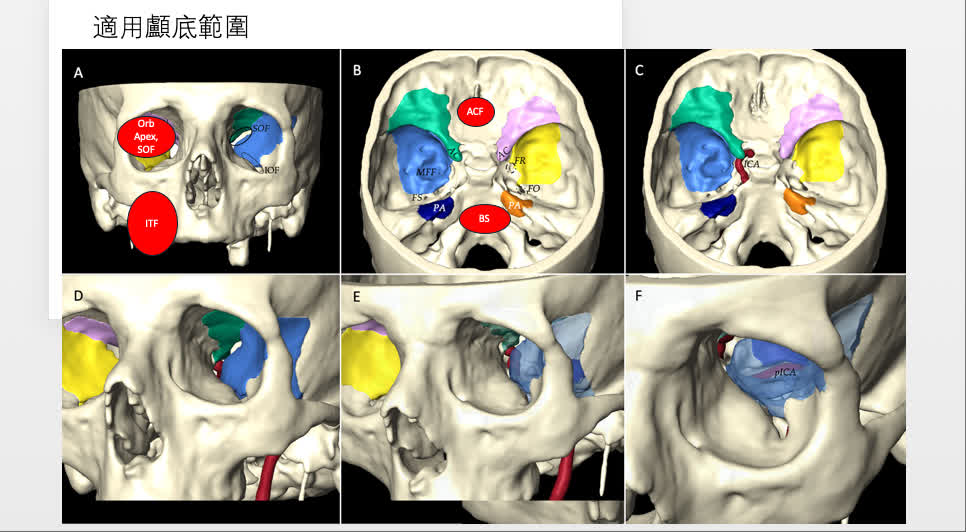

麥凱鈞醫生介紹,顱底(Skull Base)是頭顱骨的底部,結構極為複雜且緊密,是腦部與頸部連結的樞紐。此區域包含視神經、三叉神經、面部神經等重要神經,以及頸內動脈、頸靜脈等主要血管,通過多個孔洞穿梭,管控面部感覺、咀嚼、表情及腦部血液供應。若腫瘤位於顱底,可經由眼眶外側路徑,放入直徑僅4毫米的內窺鏡——約為小拇指指甲蓋的三分之一大小。該路徑不經過眼球,而是通過眼眶骨與眼球外側之間的天然空隙深入頭顱底,處理傳統開顱手術難以觸及的深處腫瘤或血管病變。麥醫生會聯同眼科醫生,將眼眶骨稍作磨平,形成一個外觀不可見的數毫米空隙,再將內窺鏡置入。

然而,麥醫生強調,該手術並非適用於所有腦瘤患者,主要取決於腫瘤位置。若腫瘤位於後腦勺或頭骨表層,僅需小切口即可切除,無須經由眼眶路徑。